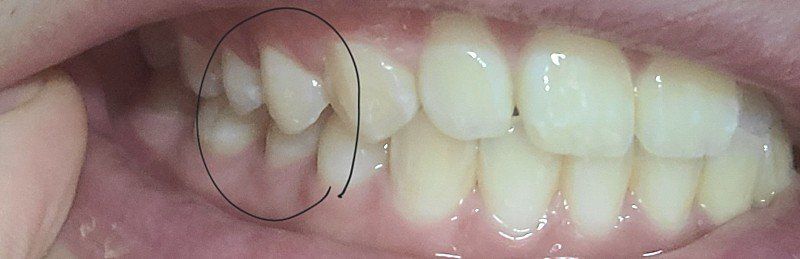

1.치아 교합이 어금니 소구치교합이 딱 안맞기도 하나요?

한쪽은 조금 떨어져있고 반대쪽은 딱 붙어있습니다

살짝 떨어져있는게 정상인지 딱 붙어있는게 정상교합인지 모르겠습니다

• 1번 째 사진

1. 치아와 치아가 서로 맞물릴 때 점과 점으로 만나 교합을 이룹니다. 따라서 사진에서 보는 바와 같이

약간의 공간이 생기는 것은 정상 범주에 속합니다.